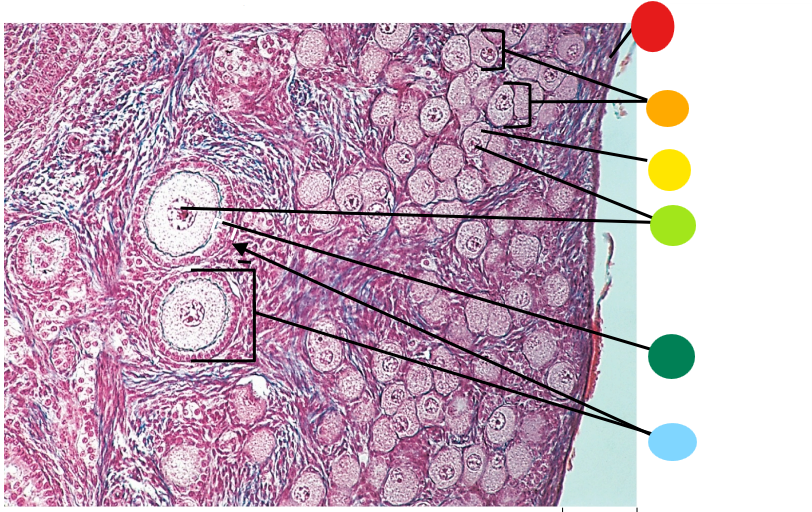

Lab H: Female reproductive histology

red

tunica albuginea

orange

primordial follicles

yellow

follicular cells

light green

primary oocyte

dark green

granulosa cells

light blue

primary follicles

what is this?

ovary